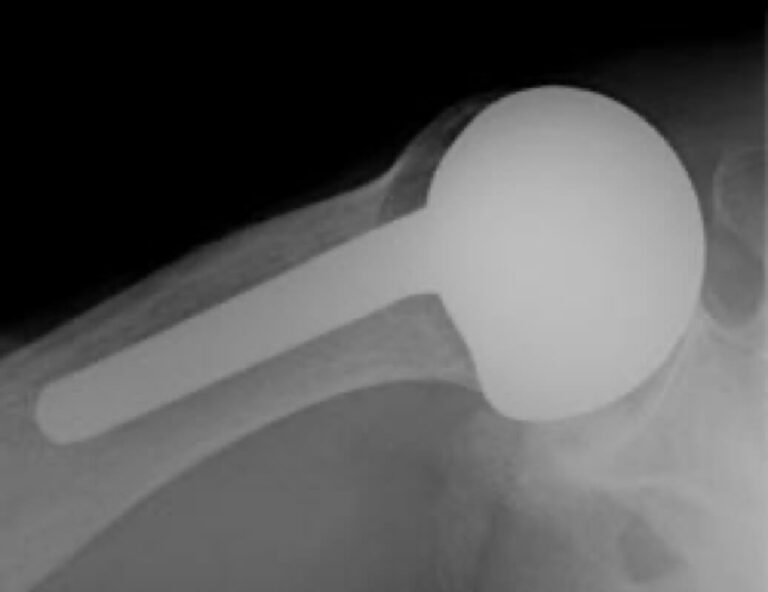

DePuy, Global Advantage CTA